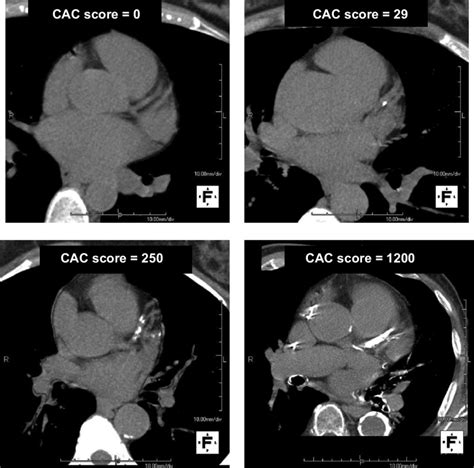

calcium score of 250